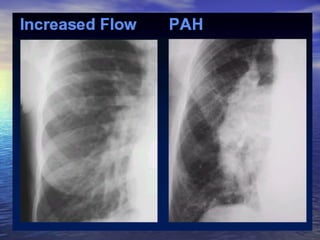

left atrium enlarged  (continue..) Increased flow               VSD  PDA                            Pulmonary arterial hypertension    + pulmonary venous hypertension    - Mitral stenosis                     .            + increased flow  - VSD, PDA